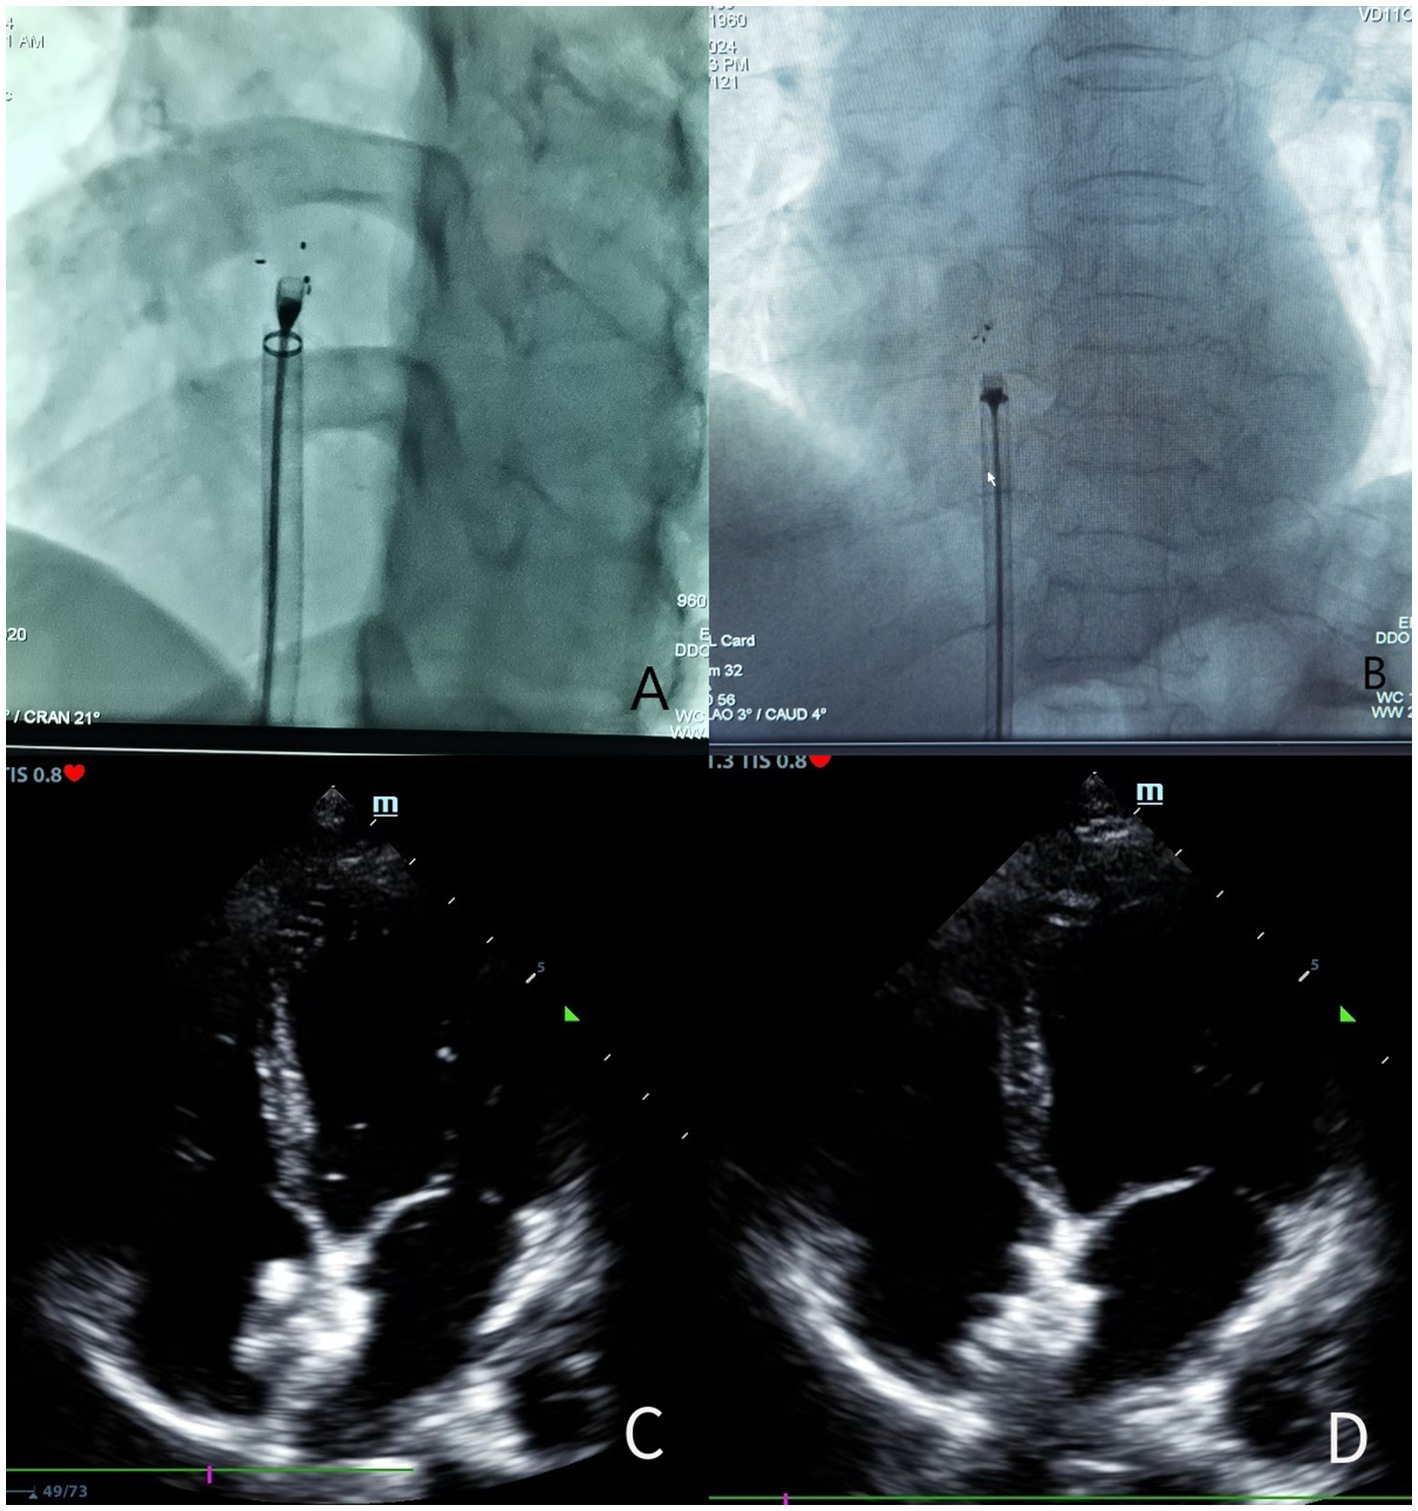

Preventive antibiotics were administered intravenously 15 min before the operation. During the operation, the patient lay flat on the operating table. Lidocaine was used for local anesthesia of the right groin. The right femoral vein path was selected, and a 6F venous sheath was inserted. Heparin was administered according to the patient’s body weight (80–100 IU/kg) (18). It was replaced with an 8.5F Swartz sheath tube and sent down to the superior vena cava. The tip of the sheath tube pointed to the atrial septum. When there was a jump, an attempt was made to send the guide wire through the foramen ovale into the left pulmonary vein. Then, the hardened guide wire and the 10F-12F delivery sheath tube were inserted into the occluder. After releasing the left atrial front umbrella, the sheath tube was withdrawn; subsequently, the right atrial rear umbrella was released. After confirming that the occluder had no displacement, subsequent operations were carried out. For absorbable occluders, after confirming through ultrasound that the occluder is attached to the left atrial septum, the tail of the line is tightened to shape the occluder and make it adhere tightly to the atrial septum, and then subsequent operations are carried out (Figure 1). The delivery sheaths, metals, and absorbable occluders used during the operation were all purchased from Shanghai Shape Memory Alloy LTD or Beijing Huayi Shengjie LTD.

Figure 1. (A) Before the release of the biodegradable occluder under the X-ray line; (B) After the release of the biodegradable occluder under the X-ray line; (C) Before the release of the biodegradable occluder by TTE during the operation; (D) After the release of the biodegradable occluder by TTE during the operation.

Comparing the postoperative MIDAS scores (biodegradable occluder group: 10.45 ± 9.19 vs. metallic occluder group: 11.32 ± 9.62, p = 0.453) and the number of days of migraine attacks each month after the operation (biodegradable occluder group: 2.09 ± 1.58 days vs. metallic occluder group: 1.87 ± 1.43 days, p = 0.506) between the two groups, the differences were not statistically significant. In the biodegradable occluder group, the preoperative MIDAS scores were 37.80 ± 7.30, and the postoperative MIDAS scores were 10.45 ± 9.19, p < 0.05. The number of days of migraine attacks each month before the operation was 5.86 ± 1.54, and the number of days of migraine attacks each month after the operation was 2.09 ± 1.58, p < 0.05. In the metallic occluder group, the preoperative MIDAS scores were 40.05 ± 7.75, and the postoperative MIDAS scores were 11.32 ± 9.62, p < 0.05. The number of days of migraine attacks each month before the operation was 5.92 ± 1.84, and the number of days of migraine attacks each month after the operation was 1.87 ± 1.43, p < 0.05. The MIDAS scores before and after the operation and the number of days of migraine attacks each month in both groups reached statistical significance (Figure 1).